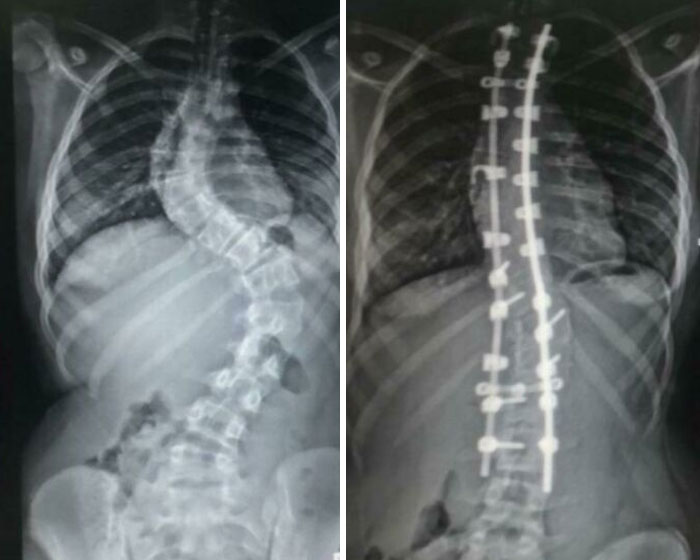

#13 My Spine Before And After Spinal Fusion

Image source: MoustacheManLOL